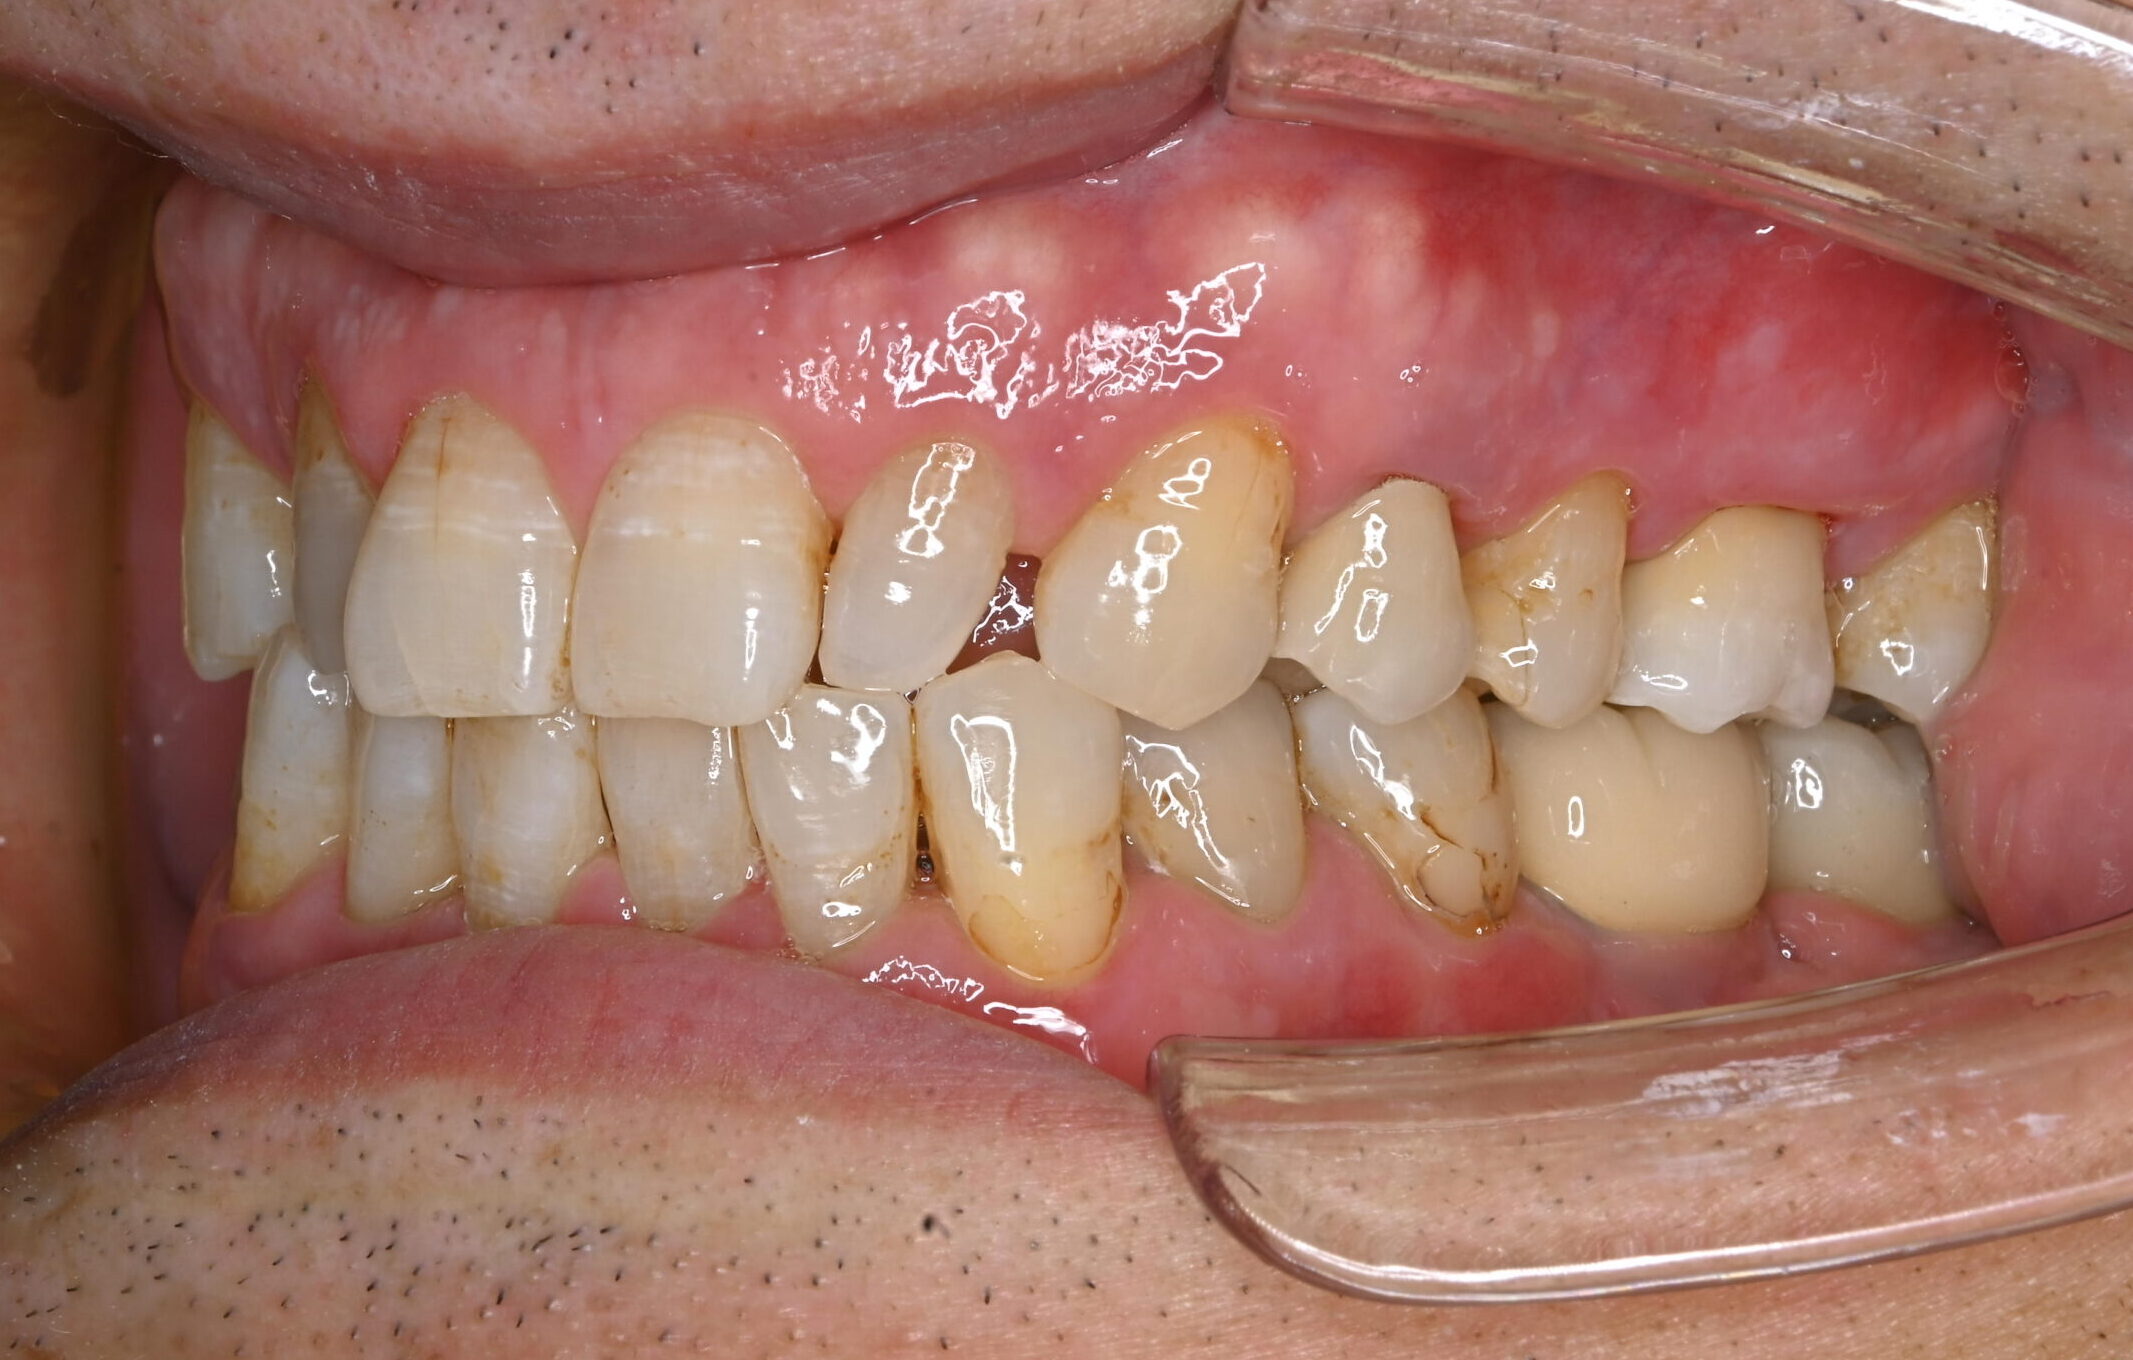

after

治療後

症例写真 after

まず右下6番の抜歯、インプラント埋入手術、上部構造の装着を行い、次いで左下6番の治療を右下同様に進めました。

上部構造装着後10年以上経過しますが、定期的なメインテナンスと患者さんの日々のケアの甲斐あって、現在まで良好な経過をたどっています。